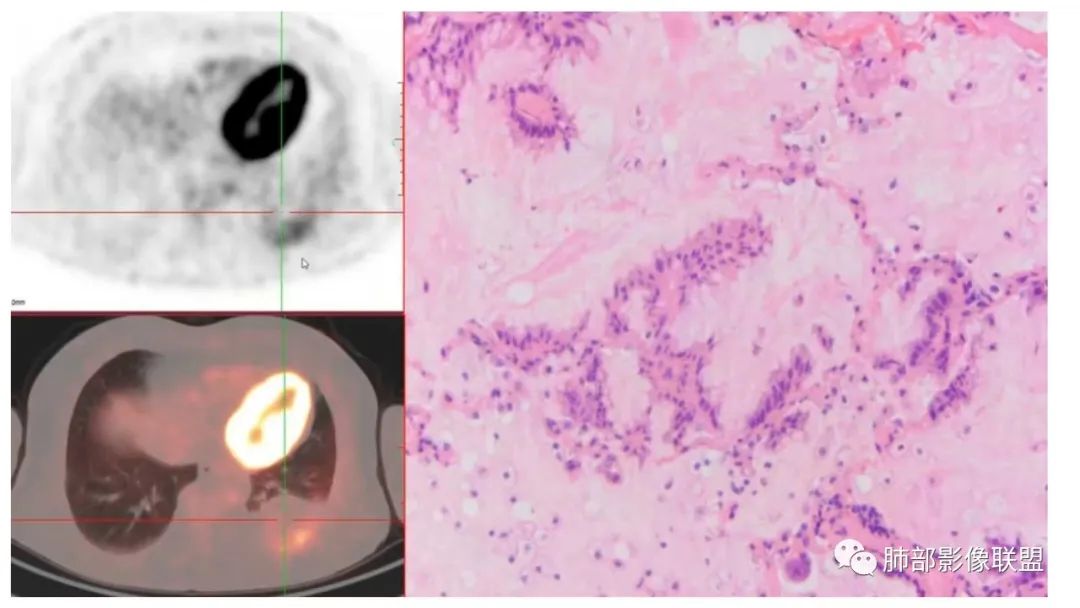

4、增强后不均匀强化,存在低强化区呈弱强化或无强化,因此可见“血管造影征。”血管毛糙与肺炎有统计学差异。

9.粘液腺癌的变化规律:结节缓慢发展而来,向周围播散形成斑片后可快速进展,有时支气管镜后或粘液排出后局部可形成好转的假象。病灶可沿肺泡和支气管播散。